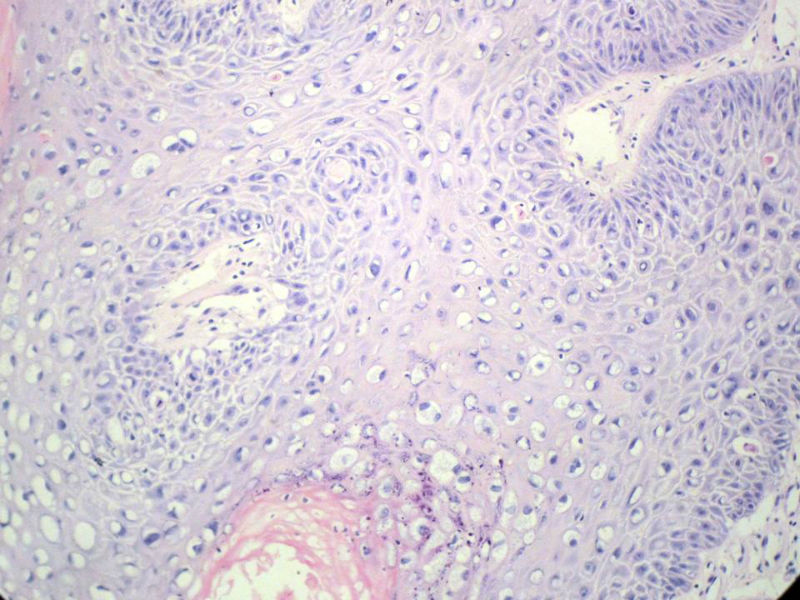

男,72岁,右耳听力下降两个月,检查右外耳道有黄豆大肿物,表面乳头状,手术切除。

请教:此例的组织像有恶变可能性吗?

乳头状瘤,有轻度异形,有恶变倾向

乳头状瘤,上皮内可见挖空样细胞,建议HPV检测